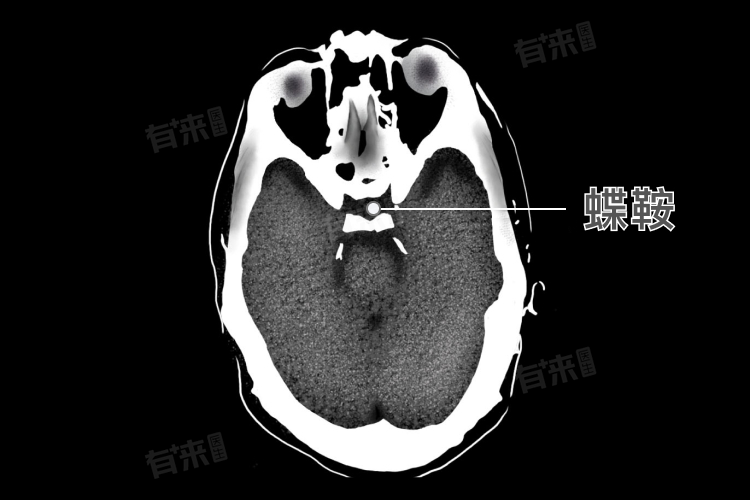

1、蝶鞍:蝶鞍是蝶骨中央部分的一个凹陷,形似马鞍,包括前床突、交叉前沟、鞍结节、垂体窝、鞍背和后床突等结构。

蝶鞍区的形态变异较多,但通常具有一些共同特征。蝶鞍的形状类似马鞍,中部凹陷为垂体窝,窝的前方隆起为鞍结节,鞍结节两侧的小骨突为中床突。窝的后方为鞍背,其两侧角向上突起为后床突。此外,蝶鞍区还可能存在鞍桥、颈动脉床突孔等形态变异。

蝶鞍区的大小因人而异,但通常具有一定的范围。蝶鞍的前后径约为11-12mm,深度约为6-9mm,鞍底横径约为14-15mm。